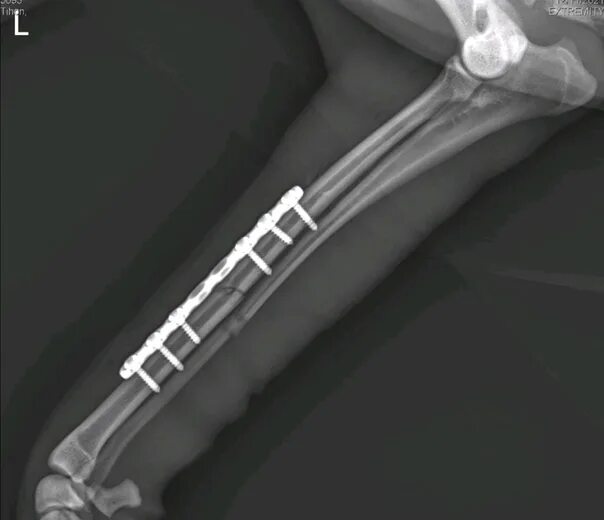

Остеосинтез мрт